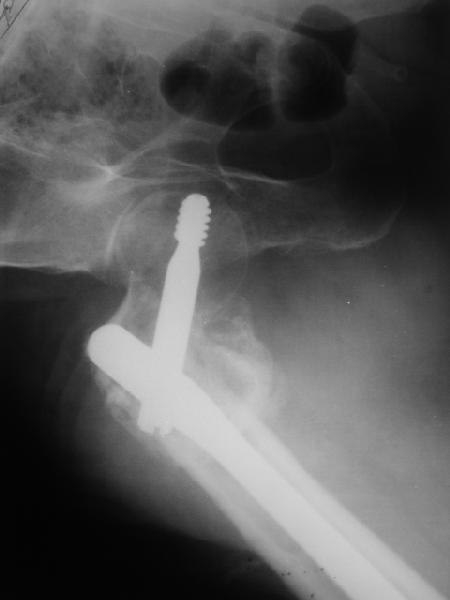

В приложении пример пациента, близкого по картине к тому, что представил Виктор (варус и смещение периферического отломка на поперечник кзади). Сделали как раз то, что Виктор исходно намеревался - аппаратная коррекция и затем гамма.